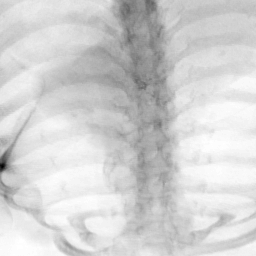

Exp. 3: Adult thorax data: To show the versatility of our approach we also apply it to adult thorax scans. For this experiment no organ specific training is performed but the whole volume is used. We evaluate reconstruction performance similar to Exp. 1 and Ti^^subscript𝑇𝑖\hat{T_{i}} prediction performance when ΩΩ\Omega is projected on an external plane, comparable to X-Ray examination using C-Arms. The latter provides insights about our method’s performance when applied to interventional settings in contrast to motion compensation problems. 60 healthy adult thorax scans were randomly selected, 51 scans used for ΩtrainsubscriptΩ𝑡𝑟𝑎𝑖𝑛\Omega_{train} and nine scans used for ΩvalidationsubscriptΩ𝑣𝑎𝑙𝑖𝑑𝑎𝑡𝑖𝑜𝑛\Omega_{validation}. Each scan is intensity normalised and resampled in a volume of 200×200×200200200200200\times 200\times 200 with spacing 1mm×1mm×1mm1𝑚𝑚1𝑚𝑚1𝑚𝑚1mm\times 1mm\times 1mm. Using the Fibonacci sampling method, 25 sampling plane of size 200×200200200200\times 200, evenly spaced between -50 and +50, were rotated over 500 normals. Training took approximately 20 hours for 60 epochs. Fig. 4c shows an example reconstruction result gaining 28dB PSNR with additional SVR. Ti^^subscript𝑇𝑖\hat{T_{i}} prediction takes approx. 20 ms/slice for this data.

Figure 4: (a): Comparison of a single slice from raw low-dose thorax CT data; (b): reconstruction based on SVRNet Ti^^subscript𝑇𝑖\hat{T_{i}} regression; (c): SVR initialized with SVRNet transformations after four iterations of SVR; (d): PSNR of (b) and (c) compared to (a). (e): shows a projection of an unseen pathological test CT volume as DRR and (e) shows a DRR at the location predicted by our method when presented with the image data in (e).

We use Siddon-Jacobs ray tracing [15] to generate Digitally Reconstructed Radiographs (DRRs) from the above described data. For training, we equally sample DRRs on equidistant half-spheres around 51 CT volumes at distances of 80cm, 60cm, and 40cm, between 90superscript90-90^{\circ} and 90superscript9090^{\circ} around all three co-ordinate axes. For validation, we generate 1000 DRRs with random rotation parameters within the bounds of the training data at 60cm distance from the volumetric iso-centre. We trained on healthy volunteer data and tested on nine healthy and ten randomly selected pathological volumes (eight lung cancer and two spinal pathologies). Our approach is able to predict DRR transformations relative to the trained reference co-ordinate system with an average translation error of 106mm and 5.6superscript5.65.6^{\circ} plane rotation for healthy patients, and 130mm and 7.0superscript7.07.0^{\circ} average error for pathological patients. An example is shown in Fig. 4e,f. Note that these values are good enough to robustly initialize intensity-based registration refinement. SVRNet prediction can be improved by generating a denser training data set, in particular, in more equidistant half-spheres.